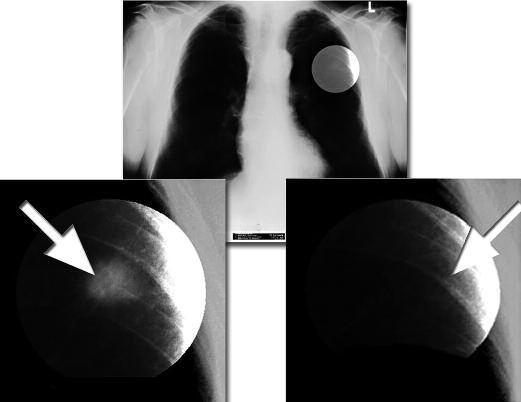

Radiografia di un cancro alle ossa

Da notare lo sviluppo del cancro in prossimità dell’articolazione, nell’area di crescita di questo organo.

AA. Un tumore cancerogeno sviluppato in un topo, non in grado di produrre vitamina C che viene sottoposto ad una dieta carente di vitamina C.

Notare che il confine diffuso del tumore (freccia) con le cellule tumorali che facilmente invade i tessuti circostanti

BB Con l’integrazione di vitamina C, i topi dello stesso esperimento hanno eretto una forte barriera di tessuto connettivo attorno al tumore, confinandolo alla posizione originale E' evidente da questa immagine che è improbabile che i tumori incapsulati invadano il tessuto circostante e creino una metastasi.